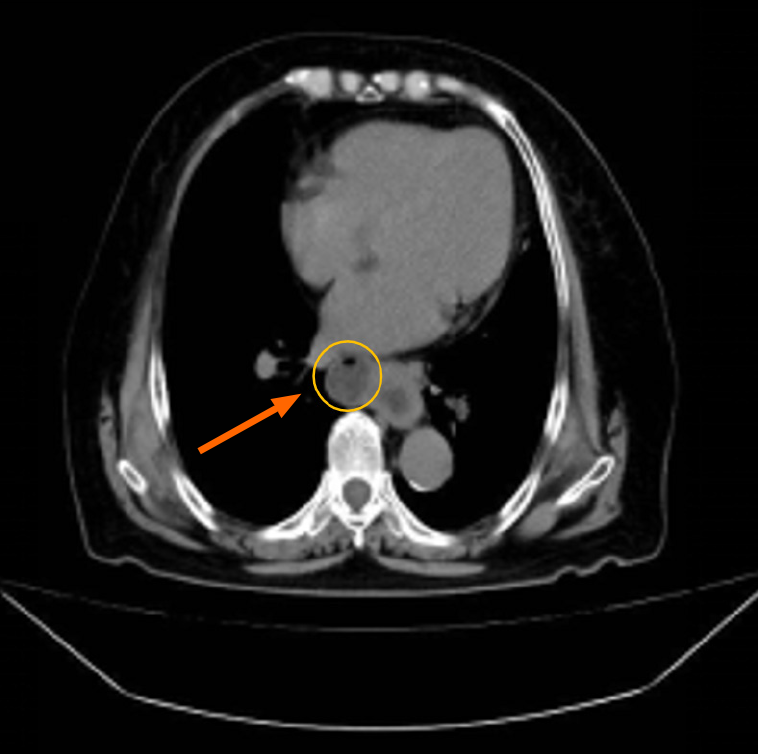

Figure 1 Computed tomography image of the whole abdomen.

The cystic bulge on the right side of the middle esophagus was considered an esophageal diverticulum, and local thickening of the lower esophagus was observed.